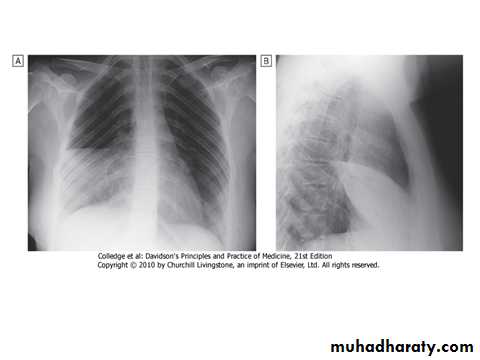

A chest X-ray:

Usually provides confirmation of the diagnosis. In lobar pneumonia, a homogeneous opacity localized to the affected lobe or segment usually appears within 12-18 hours of the onset of the illness (Fig. above). Radiological examination is helpful if a complication such as :Parapneumonic effusion.

Intrapulmonary abscess formation .

Empyema is suspected.